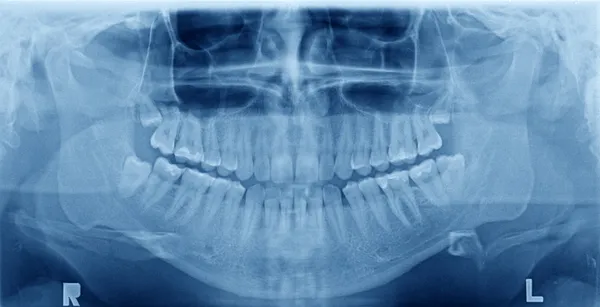

8. Please, include X- ray before obtuariation.

Important! X-ray after obturation.